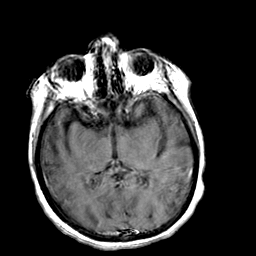

Creutzfeld-Jakob disease: gadolinium enchanced T1-Weighted MR -- Slice #11

[Home][Help][Clinical] Slice 11